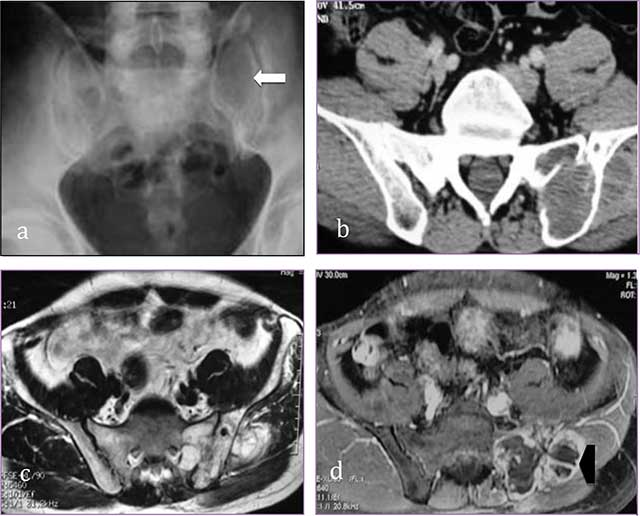

Figure 4

Sacral chondrosarcoma. (a) Plain radiograph of pelvis shows an ill-defined osteolytic lesion of left sacrum (white arrow). (b) transversal CT scan shows extension through the left sacroiliac joint, the ilium and the gluteal muscles. (c, d) MR: transversal T2-WI, transversal T1-WI after gadolinium contrast injection show a lobulated mass predominantly of high signal intensity on T2-WI with ring-and-arc enhancement (arrowhead).